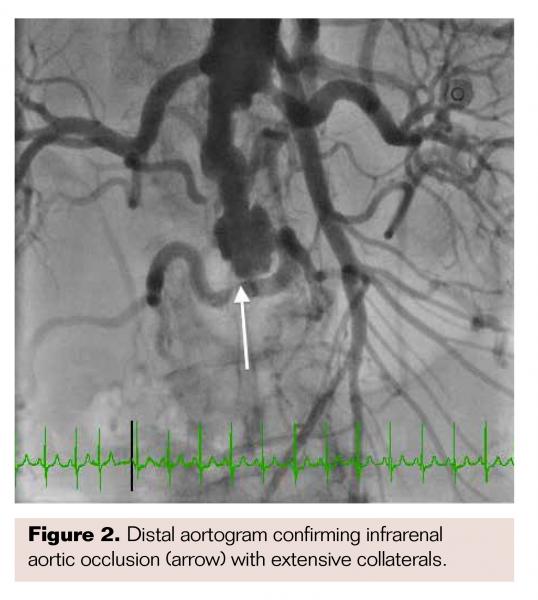

Multiple guides were used to engage the RCA via radial approach but with inadequate support to advance a balloon across the lesion, despite the use of a Guideliner (Vascular Solutions) as a guide extension and an Emerge balloon (Boston Scientific) as an anchor balloon in the conus branch artery.After prolonged attempts that ultimately failed, PCI of the RCA via radial approach was aborted. Descending aortogram revealed an ulcerated eccentric lesion below the renal arteries with 100% distal occlusion (Figure 2). Extensive collaterals from the lumbar and mesenteric arteries were noted to reconstitute bilateral external iliac arteries. At this point, due to failed revascularization of the RCA from radial approach, endovascular revascularization of the aortoiliac occlusion was planned to allow PCI with better guide support from the femoral approach. An interim computed tomography angiography of the descending aorta and lower extremity runoff confirmed the findings on the aortogram with no suggestion of a thrombosed abdominal aortic aneurysm.